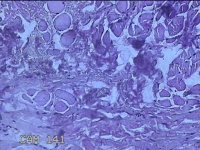

前额部结节

性别

男

年龄

26岁

临床诊断

皮脂腺囊肿

一般病史

发现前额部结节3年余。

标本名称

大体所见

灰白暗红色结节0.8x0.7x0.2cm一个,表面糜烂。